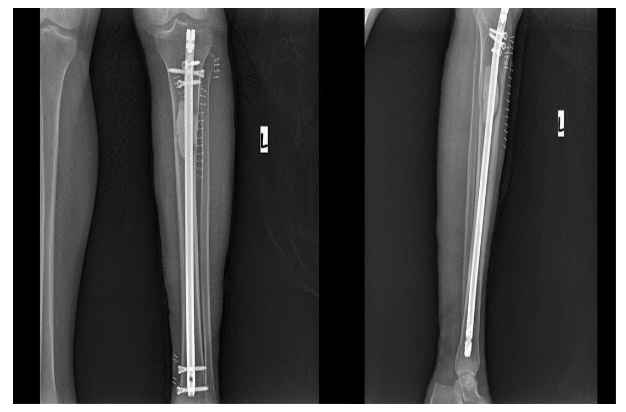

Post-surgery: The X-ray shows the tumor being removed, the resulting cavity being filled with bone cement, and a closed titanium nail being implanted.